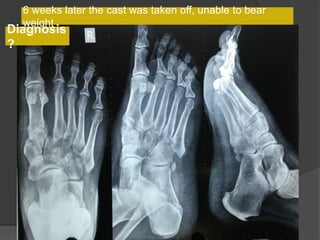

6 weeks later the cast was taken off, unable to bear

weight

Diagnosis

?

Lisfranc fracture- dislocation

Bony or ligamentous injury involving the tarsometatarsal

6 weeks laterthe cast was taken off, unable to bear weight Diagnosis ?

Bony or ligamentousinjury involving the tarsometatarsal joint complex